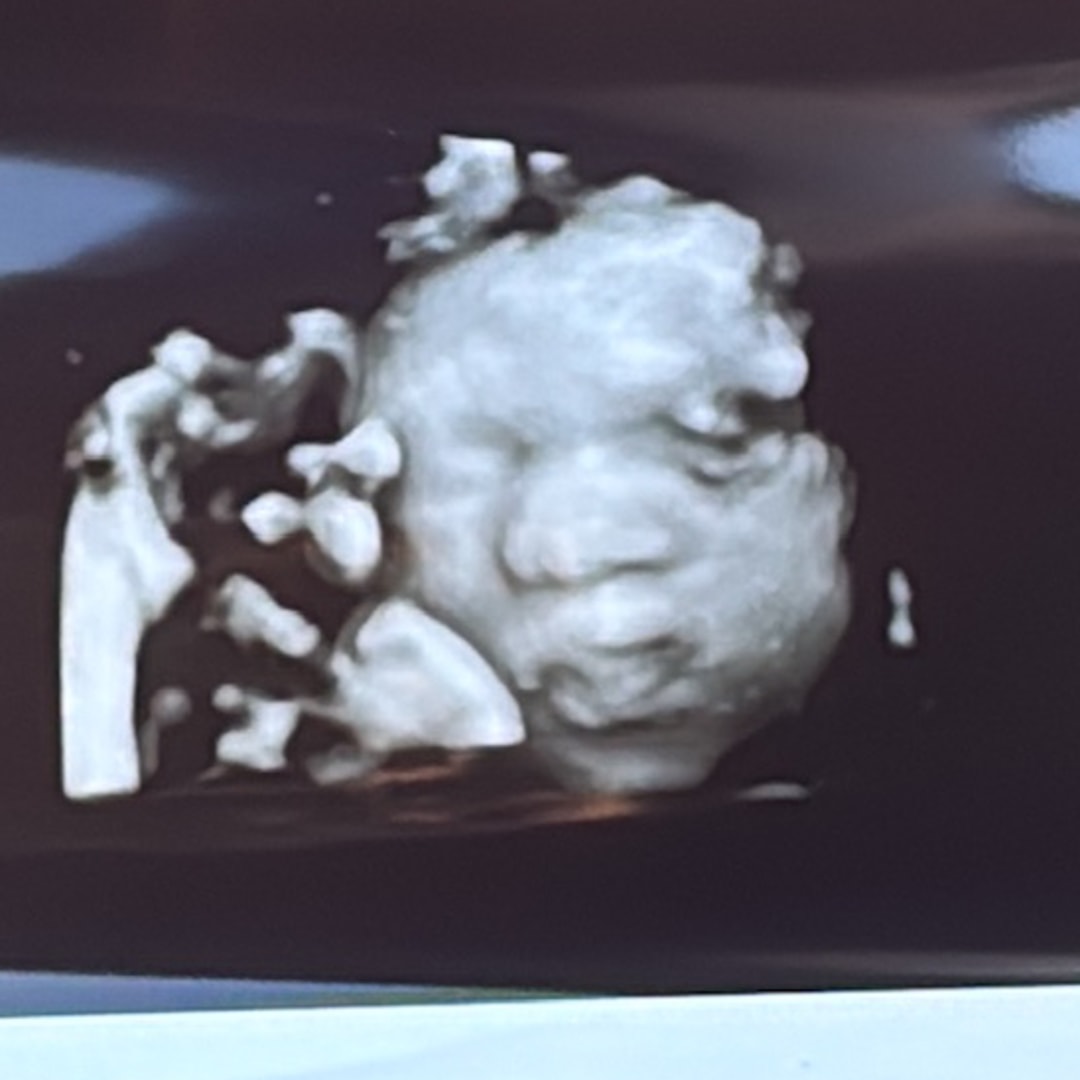

Gina Adjei & Edwin Afranie

January 7, 2026